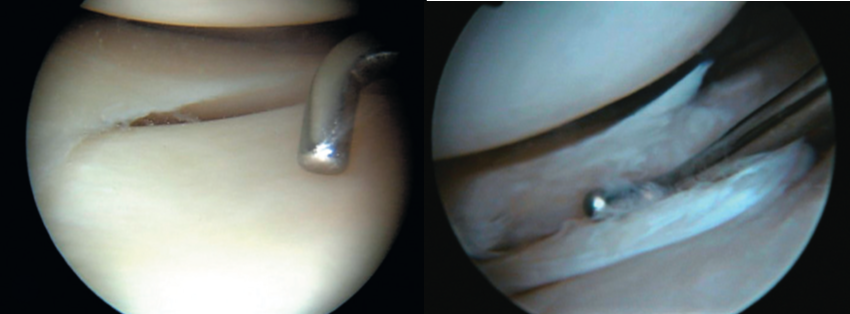

Ligamento Cruzado Anterior

Es uno de los principales ligamentos de rodilla y el principal restrictor del desplazamiento anterior de la rodilla, se lesiona generalmente al cambiar de dirección o girar la rodilla al correr, al saltar y caer de tal forma que hay una torsión de la rodilla.

Las roturas de este ligamento hacen necesaria su reconstrucción artroscópica usando injertos propios (autoinjerto) o injertos externos (aloinjertos) y una recuperación prolongada antes de la reincorporación al deporte.